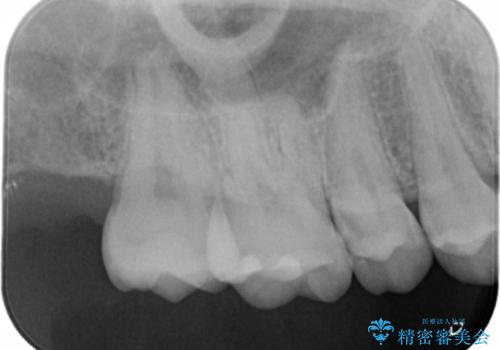

検査の結果、症状はないものの右上の奥歯に虫歯が見つかりました。

局所的に深い虫歯が確認されましたが、神経は温存することができました。

歯と歯の間から広がる虫歯は目視では確認しにくいため、定期的にチェックし悪化を予防することが大事です。